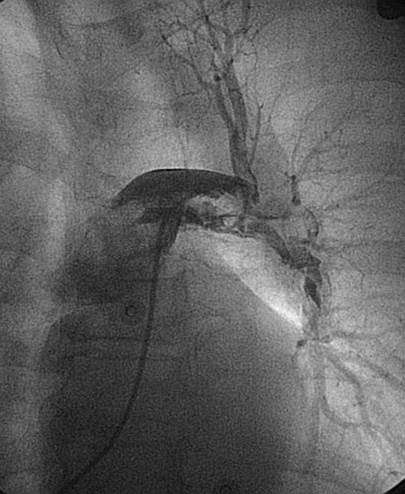

Angiografía de la arteria pulmonar izquierda realizada con un catéter en espiral de 6 F en ángulo, que demuestra la presencia de un trombo de gran tamaño dentro de la arteria pulmonar izquierda y en las bifurcaciones lobulares intermedia e inferior.

Se efectuó una trombectomía reolítica con el catéter PE de AngioJet® mediante un catéter guía multifunción de 8 F a través de una guía de angioplastia hidrófila de 0,035’’.

Angiografía pulmonar izquierda realizada tras una trombectomía reolítica en la que se muestra la mejora del índice de perfusión y obstrucción.